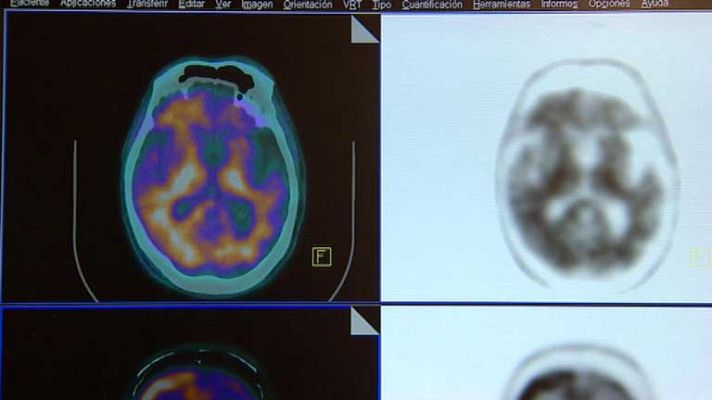

Vencer el Alzheimer sigue siendo un reto para los científicos. Más de 400 expertos reunidos en un congreso en Madrid han centrado sus esperanzas en los avances que permiten un diagnóstico precoz.